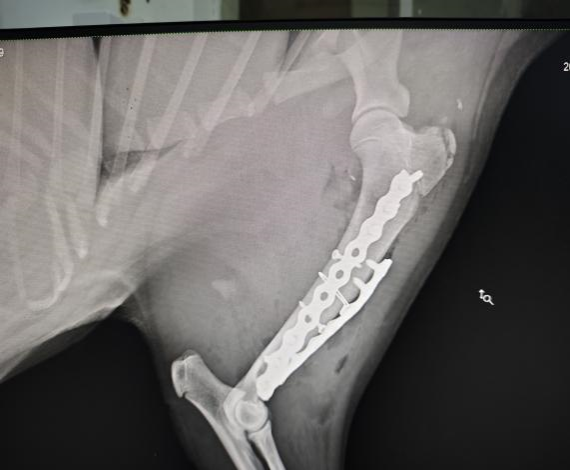

手术后左前肢侧位X光

手术团队由bat365官方网站教学动物医院院长沈留红、动物外科专家石先鹏、动物内科专家巫晓峰、医生陈善瑜和罗皓、麻醉医生邓聪辉、手术助手王郡东、助理唐清婷、张涵艺、钱琳、王均、李鑫等组成,并与动物园动物疾病预防组刘俊卿副经理团队一道组成会诊专家组,确定麻醉和手术方案。外科专家石先鹏凭借丰富的经验和精湛的技术,对水豚肱骨进行了精确的复位和固定。手术全程在严格的无菌条件下进行,确保了安全性和成功率。